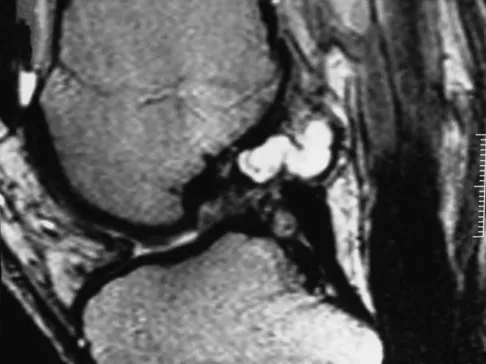

A 35-year-old patient has right hip pain. Figures 34a and 34b show the coronal MRI scan and the biopsy specimen. What is the most likely diagnosis?

Correct Answer: Osteonecrosis

Explanation:

Alcohol abuse, steroids, Caisson disease, sickle cell disease, and radiation therapy are the leading causes of nontraumatic osteonecrosis of the femoral head. Arlet J: Nontraumatic avascular necrosis of the femoral head: Past, present, and future. Clin Orthop 1992;277:12-21.